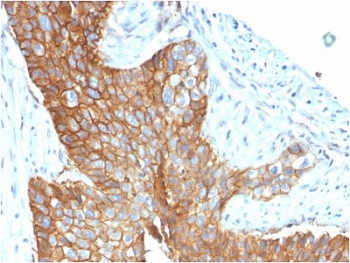

CD63 Antibody / LAMP-3 [orb2637613]

FACS, IF, IHC-P, WB

Human, Mouse

Mouse

Monoclonal

Unconjugated

100 μg